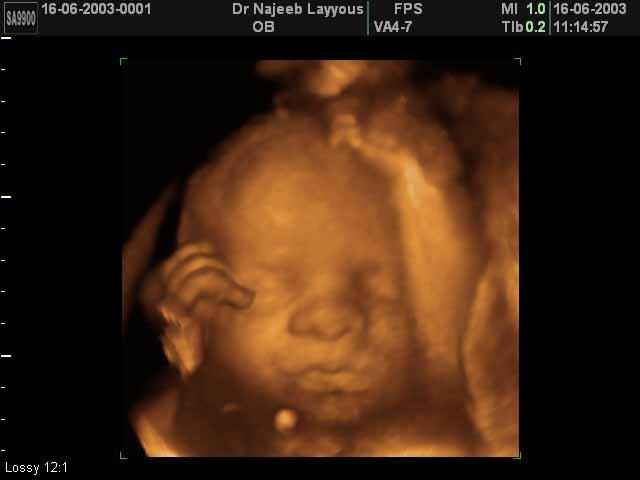

- 3D Fetal Profile Ultrasound Scan Photos

3D Fetal Face Ultrasound Scan Photos | Dr N Layyous